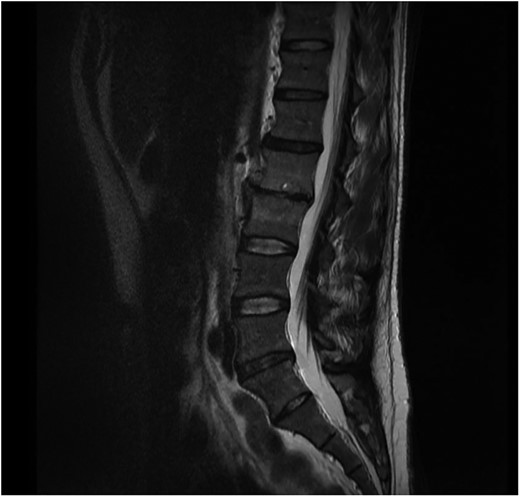

Neurosurgical advice recommended that due to the lack of neurological symptoms the patient could be treated conservatively with antibiotics. Microbiology advice was to treat the patient with IV flucloxacillin and oral rifampicin for at least 2 weeks and then to continue with oral antibiotics for at least a further 6 weeks depending on clinical improvement. Repeat bloods and MRI scans were performed to monitor the response to antibiotics (Fig. 2).

Sagital T1 MRI lumbosacral spine. 2 months later the epidural abscess has resolved and minimal marrow oedema is seen in L2 and L3 vertebra.